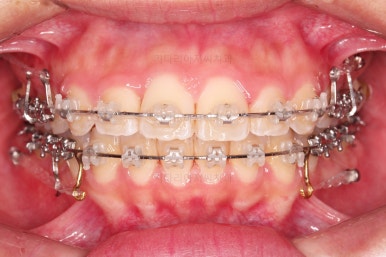

이번 환자분이 선택한 장치는 엠파워 클리어라고 하는 자가결찰 세라믹 장치입니다.

흔히들 아시는 클리피씨 장치와 동일한 종류의 장치인데, 제조국이 일본(클리피)이냐 미국(엠파워)이냐의 차이가 있습니다.

장치 부착 직후의 얼굴 모습입니다.

장치가 주는 느낌과 장치를 부착해서 변하는 입매의 느낌 참고 바랍니다.